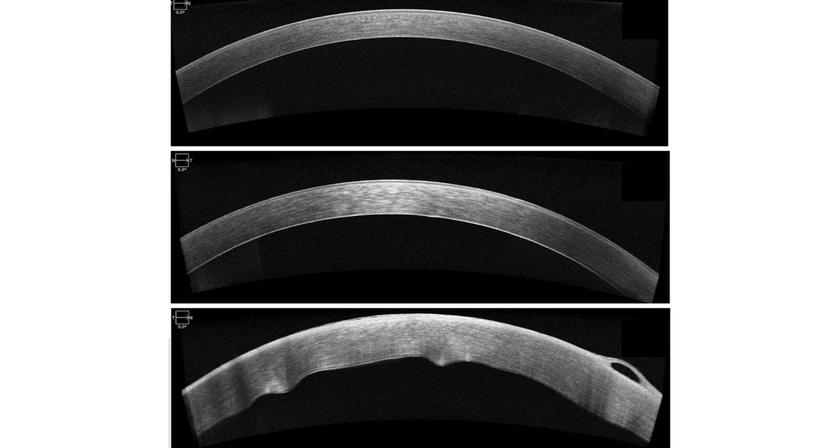

Hornhautnarben oder Unregelmäßigkeiten können ergänzend zur mikroskopischen Beurteilung am besten mittels hochauflösenden Laser-Schichtbildaufnahme (sog. OCT, optische Kohärenz Tomographie) untersucht und beurteilt werden. Auch dieses Messverfahren steht Ihnen in unserer Ordination zur Verfügung.